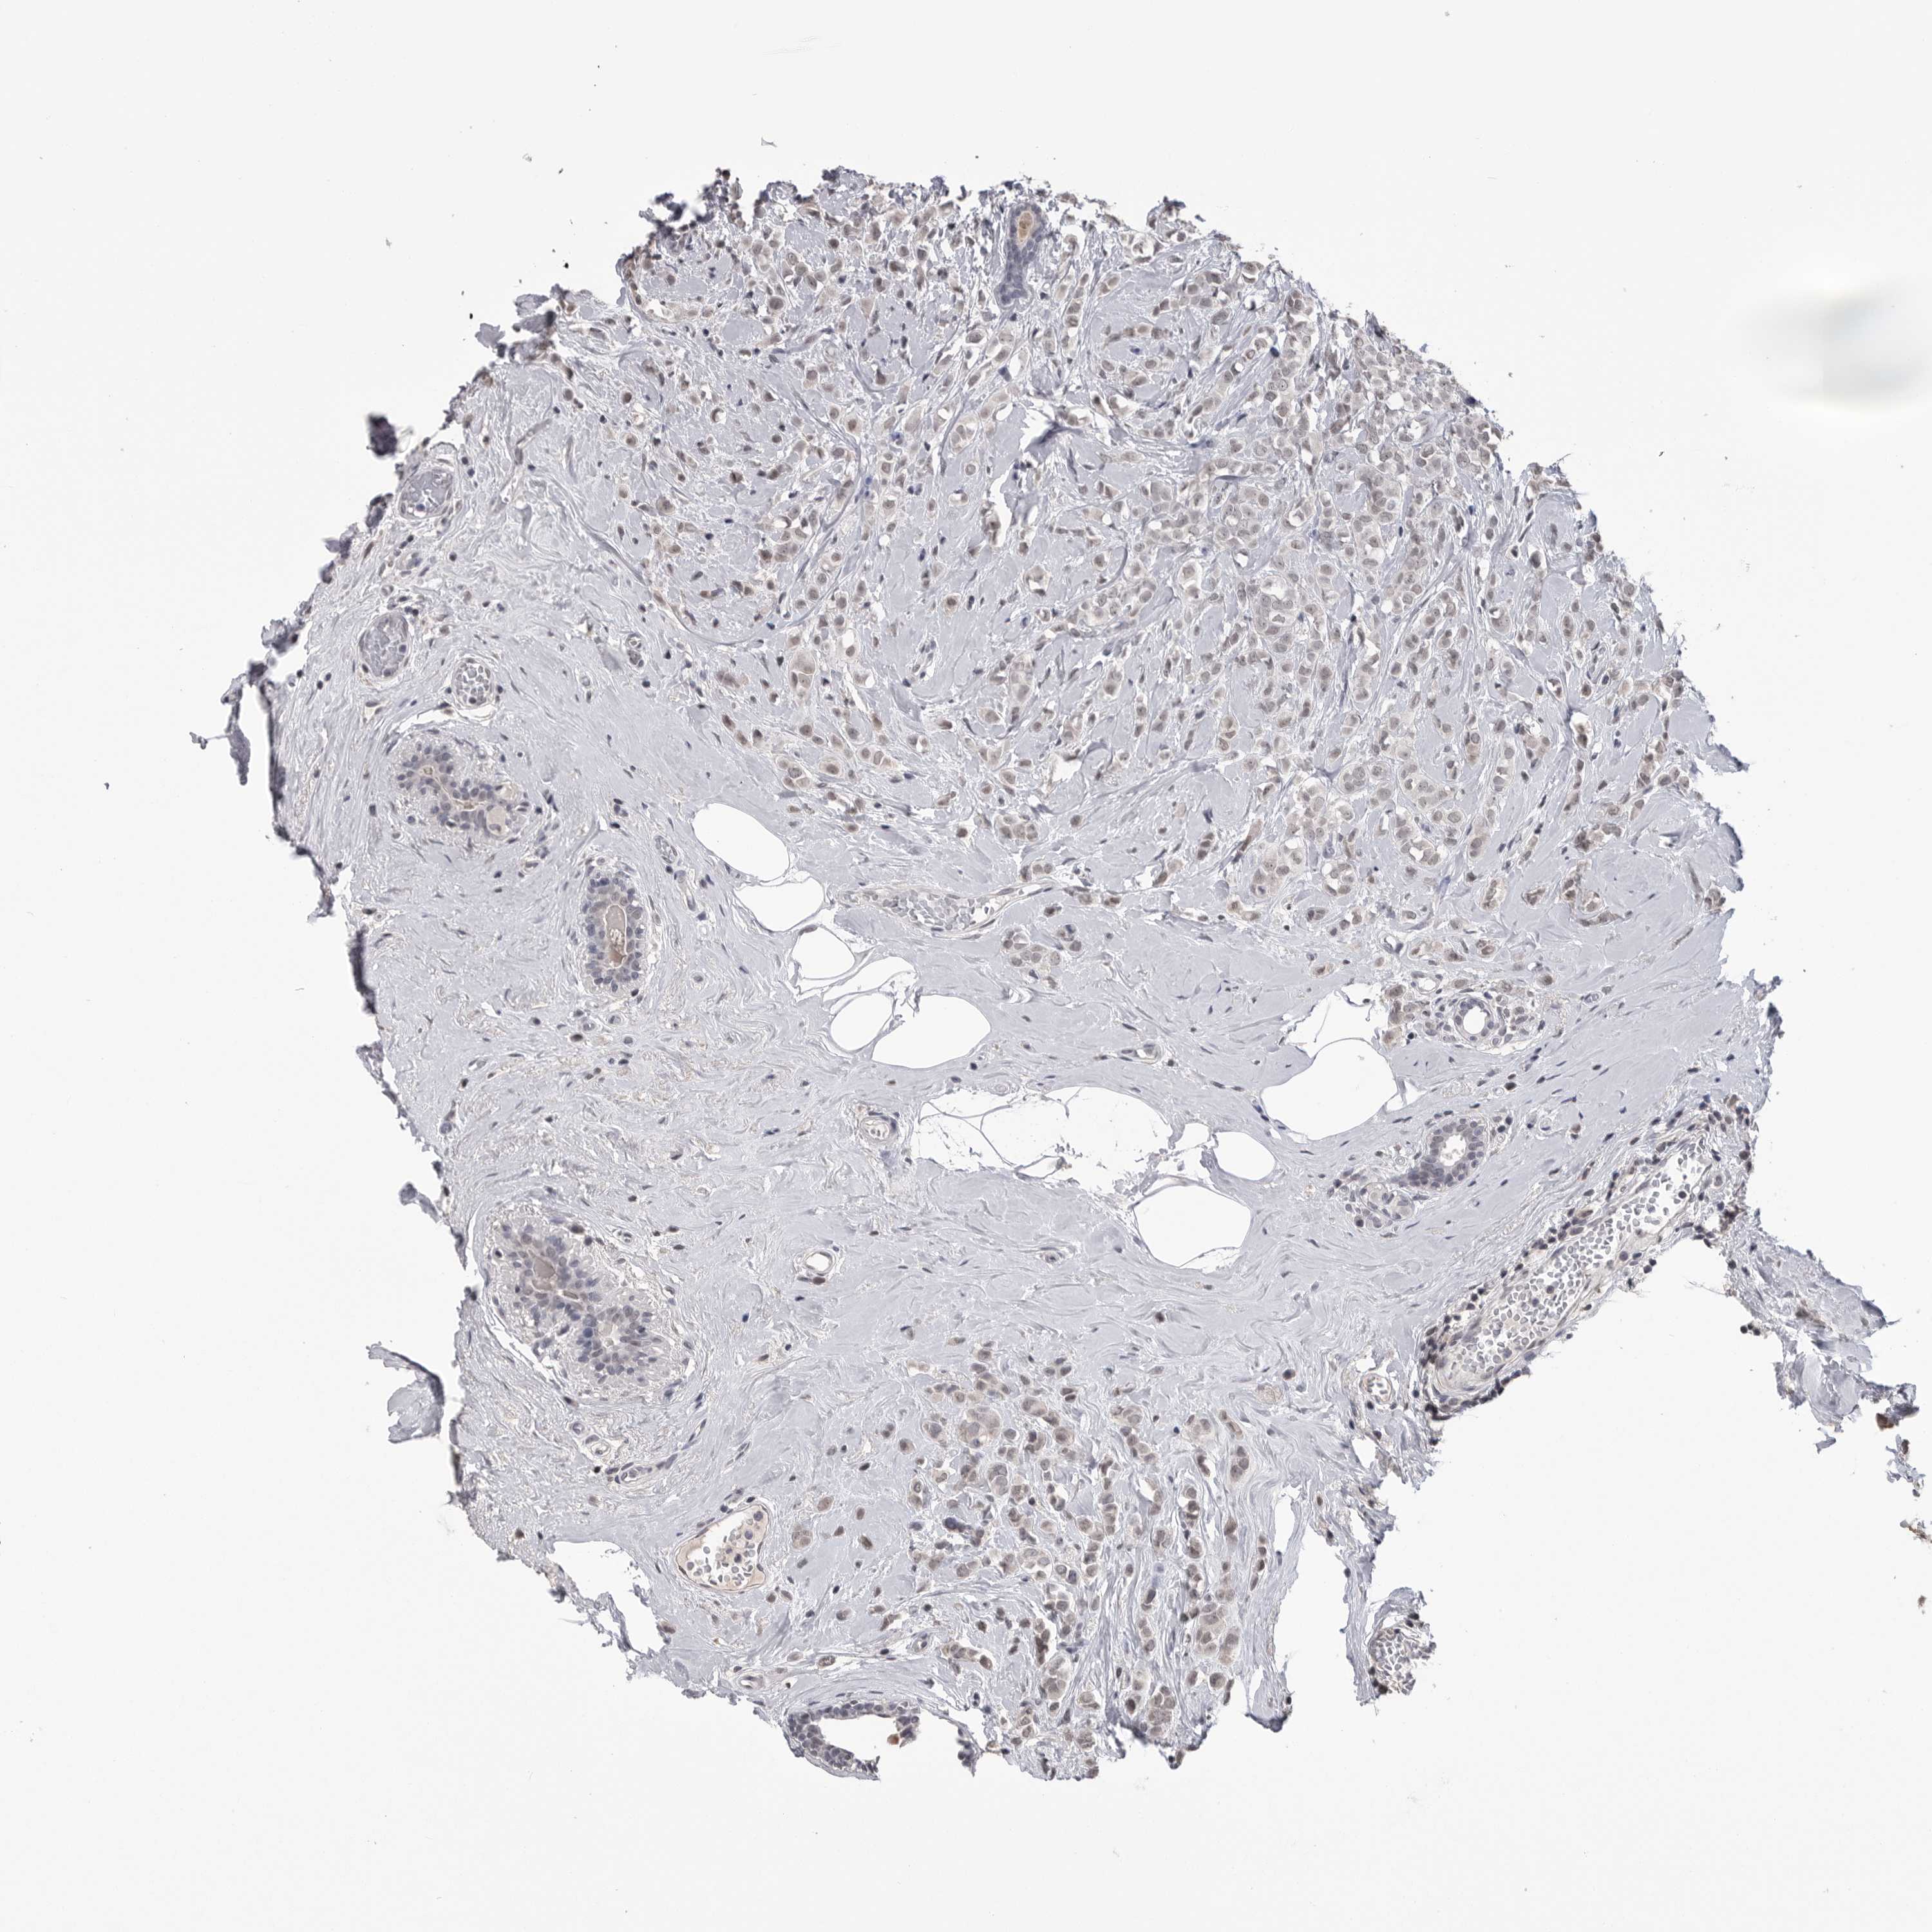

CANCER BREAST CANCER Show tissue menu

BRCA TCGA BRCA VALIDATION PROTEIN EXPRESSION